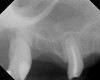

As with implant placement in general, use of a round bur is the first step in forming the osteotomy. As described above, to get verification of positioning—especially if a surgical stent is not used—a small piece of gutta percha can be placed inside this small osteotomy and a radiograph taken (Figure 1), after which the gutta percha is removed. The next step is the most critical, as it involves exposing the Schneiderian membrane. A 2-mm twist drill is used at a speed not exceeding 250 rpm, using a very light touch. Because the bone quality in the maxillary posterior is generally poor, it is usually easy to feel when the medullary bone has been breached and the dense cortical bone of the floor of the sinus has been reached. The cortical plate of the floor of the sinus should have been carefully measured with periapical radiographs presurgically, but it is usually about 1 mm in thickness. The most important and technique-sensitive part of this procedure is breaching the cortical plate of bone lining the sinus without tearing the sinus membrane. With a solid finger rest, good control, very light drilling pressure, copious irrigation, and a slow drilling speed, a slight “give” occurs once this plate of bone is breached. The full width of the twist drill should not penetrate the sinus floor; otherwise, the membrane will be torn. If it is not clear whether the membrane has been exposed, a flat-ended implant probe (Figure 2) can be used by inserting it into the osteotomy and feeling for the slight “give” or movement of the membrane. If the surgeon is not sure if the membrane is exposed, a radiographic marker can be used (Figure 3). If the membrane is significantly exposed, however, a radiographic marker should not be used, as this can inadvertently tear the membrane. The patient should also be warned not to bite down on the marker during the radiograph to avoid a membrane tear, and floss must be attached to the marker, so it can be retrieved if necessary.

After about seven or eight cycles, a radiograph should be taken to verify the apical position of the sinus membrane (Figure 4). If the sinus has been raised at least 3 mm to 4 mm, the 2.8-mm twist drill should be used to remove the remaining bone at the base of the osteotomy. The osteotomy should then be widened to the final twist drill but not yet the last drill, which is the profile drill. This will allow for easier bone tapping into the sinus. The desired height of sinus membrane elevation should be such that there is about 1 mm to 2 mm of additional apical height above the implant to be placed. Usually a 10-mm implant length is sufficient. The design of the implant should have threads close to the coronal aspect of the rough surface for better initial fixation. When using a tapered implant design, the final drill is a tapered profile drill, which is the last step before placing the implant. Because it is slightly longer than the actual implant, its use could tear the membrane. To minimize the chance of tearing the membrane, a high-speed round bur and copious irrigation can be used to flatten the end of the tapered profile drill by about 1.5 mm (Figure 9) before its use. It should be used at less than 200 rpm with limited irrigation. The groove on the profile drill corresponds to the level of the bone when used. If there is minimal native ridge height, the drill should be used to a lesser depth than the groove to make sure that the site is not drilled too deeply.

A 74-year-old man presented with only about 2 mm to 3 mm of native bone below the sinus in the No. 14 position (Figure 13). The composite graft used was an approximately 50:50 mixture of DFDBA (Bio-Oss®, Geistlich Biomaterials, www.bio-oss.com) with the addition of about 40% calcium sulfate by volume (Figure 14). The implant placed (Figure 15) was a 10-mm long, rough-surfaced, platform-shifting implant (tapered 4.2 mm to 2.8 mm), and the sinus was raised about 8 mm. The postoperative radiograph taken at 4 months (Figure 16) showed some shrinkage of the graft, but no demarcation of the old sinus floor in the area.

A 74-year-old male patient presented with about 4 mm to 5 mm of native bone in the No. 4 position (Figure 17). A composite graft, as described in Case 1, was used, as was the same implant type, but the implant was 11.5 mm in length with a taper of 5 mm to 4.2 mm. The approximately 16-month post-healed floor of the sinus was raised about 7 mm to 8 mm (Figure 18). The CBCT scan taken at 16 months postoperatively showed no change in appearance from the area of the old floor of the sinus to the new bone formed (Figure 19). Although it was endodontically involved, tooth No. 15 was not extracted, against professional advice. As can be seen in Figure 18, the No. 14 implant is acting as a bridge abutment.

This patient was a 73-year-old man with only about 3.5 mm of native bone in the No. 3 site (Figure 20). The composite graft used here was a 50:50 mixture of DFDBA and deproteinized bovine bone mineral (Osteohealth, www.osteohealth.com) with approximately 40% calcium sulfate added. The implant was the same type and length as in Case 1 above. Figure 21 shows the area on the day of placement. In the CBCT scan on the day of placement (Figure 22), the native bone and bone graft were clearly discernable. However, the postoperative radiograph taken at 6.5 months (Figure 23) showed no marginal bone loss and a significantly denser appearance than when the graft was place. The membrane was raised about 7 mm to 8 mm. The final radiograph was taken after extraction of tooth No. 2 and after extraction of tooth No. 4 and immediate implant placement.